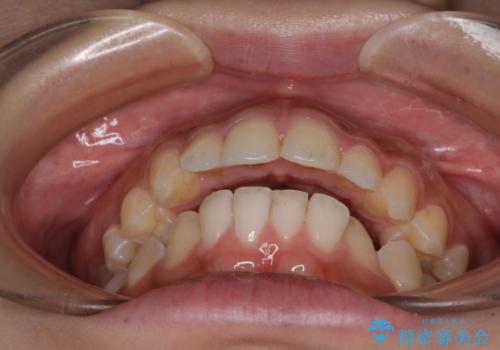

- 口元の突出感と上下前歯のズレを気にして来院された患者様です。

舌の突出癖により上下の前歯は非接触であり、更には奥歯の咬み合わせが非対称となっている状態でした。

通常は上下左右の第一小臼歯4本を抜歯することになりますが、右側臼歯部の咬合が上顎前突気味であったため、下顎右側のみ第二小臼歯を抜歯し、ワイヤー装置にて矯正治療を行うこととしました。